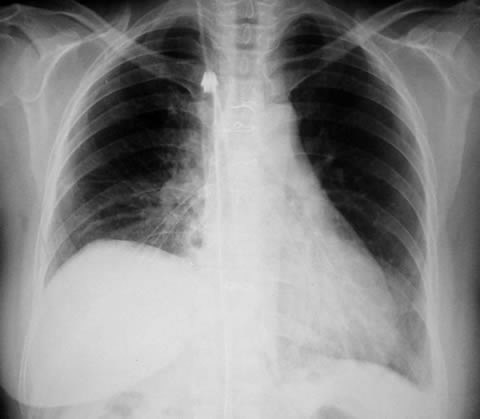

Radiología del Tórax Pos - operatorio

Radiología Pos - operatorio inmediato:

Pulmón derecho expandido, atelectasia laminar basal .

Elevación del hemi-diafragma derecho.

Un tubo torácico mediastinico para drenaje de la cavidad pleural.

Radiología Pos - operatorio tardío:

Pulmón derecho e izquierdo expandidos, aireados, senos costofrenicos libres.

Diafragmas libres.

Imagen cardiovascular normal.